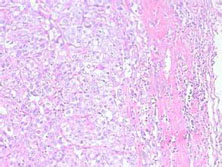

食管类癌

食管类癌起源于神经外胚层,主要发生于消化道,占消化道恶性肿瘤的0.87#xFF0...